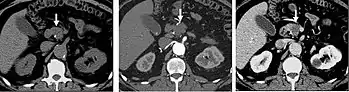

Pancreatic masses

Pancreatic masses are often evaluated using both an early arterial (to evaluate for vascular involvement and thus resectability, figure 9a) and a later “pancreatic” phase (which optimizes pancreatic parenchymal enhancement and thus is best at differentiating pancreatic tumors from pancreatic parenchyma, figure 9b). Pancreatic adenocarcinoma typically is hypoenhancing when compared to the surrounding parenchyma. Most other common pancreatic tumors are hypervascular with avid enhancement (such as pancreatic neuroendocrine tumors) and appear brighter than the surrounding pancreatic parenchyma after the injection of intravenous contrast material.